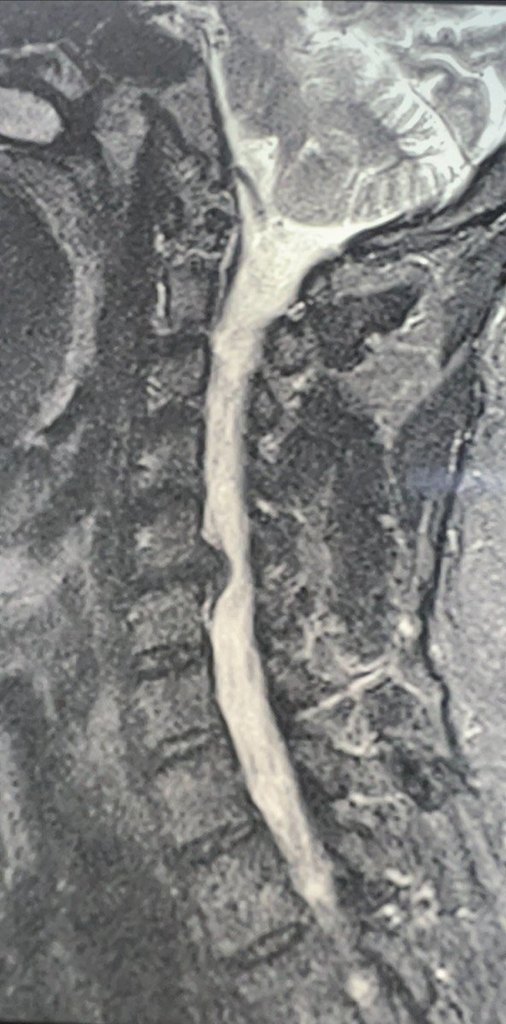

Врачи провели необходимые обследования и установили диагноз: грыжа диска С5-С6, спондилоартроз (дегенеративное поражение межпозвонковых суставов, которое затрагивает хрящи, костные ткани, связки и околосуставные мышцы), корешковый синдром (радикулит) С6 справа с чувствительными и двигательными нарушениями.

Нейрохирурги Владимир Дронов и Евгений Дронов осуществили микрохирургический передний доступ на шее. Специалисты удалили межпозвонковый диск и грыжу C5-C6 с использованием операционного оптического прибора, микрохирургической техники и инструментария. Помимо этого, была устранена компрессия спинного мозга и нервных корешков, а также установлен межтеловой кейдж — металлическая конструкция, которая размещается между двумя соседними позвонками и соединяет их между собой.

Послеоперационный период протекал без осложнений. Уже на следующий день пациенту разрешили вставать и ходить. Болевой синдром и неврологические нарушения в руке полностью разрешились через несколько дней.